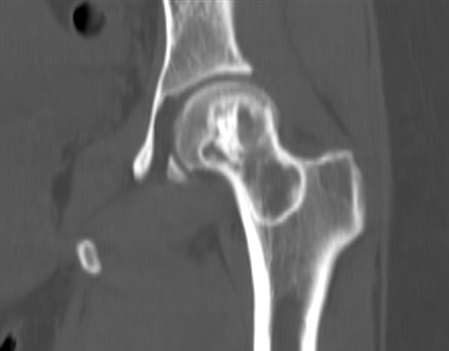

图 36.瘤软骨钙化:软骨母细胞瘤

图片

图 37.瘤软骨钙化:内生软骨瘤